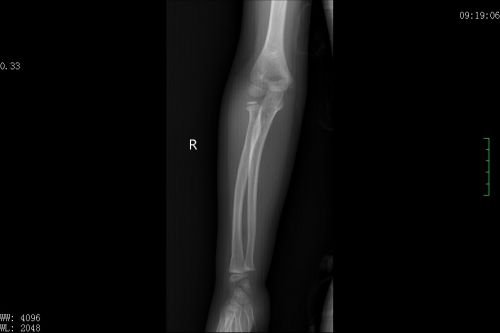

术前x片显示,右侧肱骨外髁骨折。